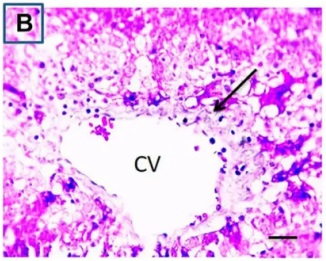

Put the liver tissue section under a microscope, and you can see that cisplatin can cause liver congestion (the blood that should return to the heart is blocked and stagnates in the hepatic veins), cell degeneration (vacuoles appear, which is the earliest change in cellular injury), apoptosis and necrosis, but these conditions can also be alleviated by using Ganoderma lucidum.

Figure 2 Effects of cisplatin and Ganoderma lucidum on hepatocytes